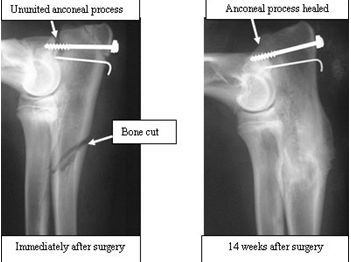

Elbow dysplasia6